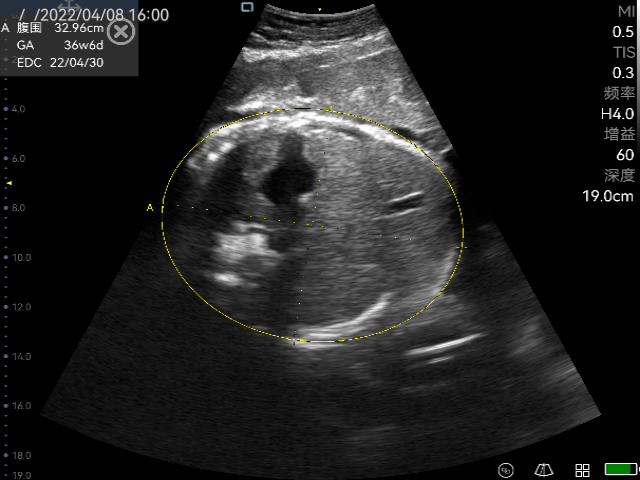

Obstetric ultrasonography is one of the routine prenatal examination items. The ultrasonic diagnostic instrument is used to scan various sections of the human body. According to the amplitude of the echo signal, real-time imaging is performed on the monitor, so it can detect the uterine appendages and the fetus. Through the biological measurement of the fetal head, abdomen, long bones, etc., the gestational age and the size of the fetus can be estimated. Through the observation of real-time dynamic ultrasound images, it is possible to detect whether the fetus has structural abnormalities, determine the degree of fetal malformation, evaluate the prognosis, whether clinical treatment is required to preserve fetal survival. For pregnant women with no abnormal performance within ten weeks, no ultrasound examination is required. For older and high-risk pregnancy, obstetric ultrasound examination must be performed regardless of the gestational age, which not only ensures the safety of the fetus, but also prepares for delivery. Ultrasound is widely used in obstetrics because of its non-radiation, simple operation, flexibility and convenience, high resolution, and moderate examination price.

The practical application of P50 in obstetrics

Perioperative period is helpful for doctors to assess the real-time labor processes of the placenta, amniotic fluid etc.

Ultrasonography in early, middle and third trimester, obstetric Doppler ultrasound, normal twin pregnancy, ultrasound diagnosis of common fetal structural malformations, twin pregnancy complications, abnormal pregnancy, abnormal pregnancy appendages, real-time monitoring of midwifery, etc.